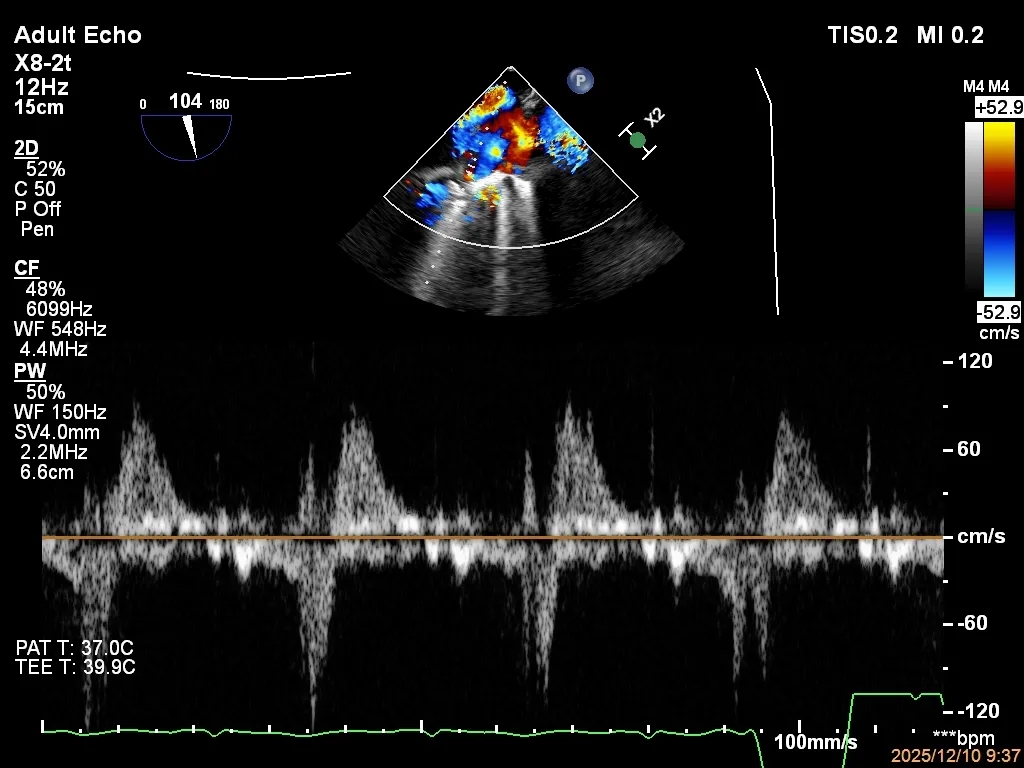

四条肺静脉均可测及收缩期反向血流

肺静脉收缩期逆流消失,频谱形态基本恢复正常